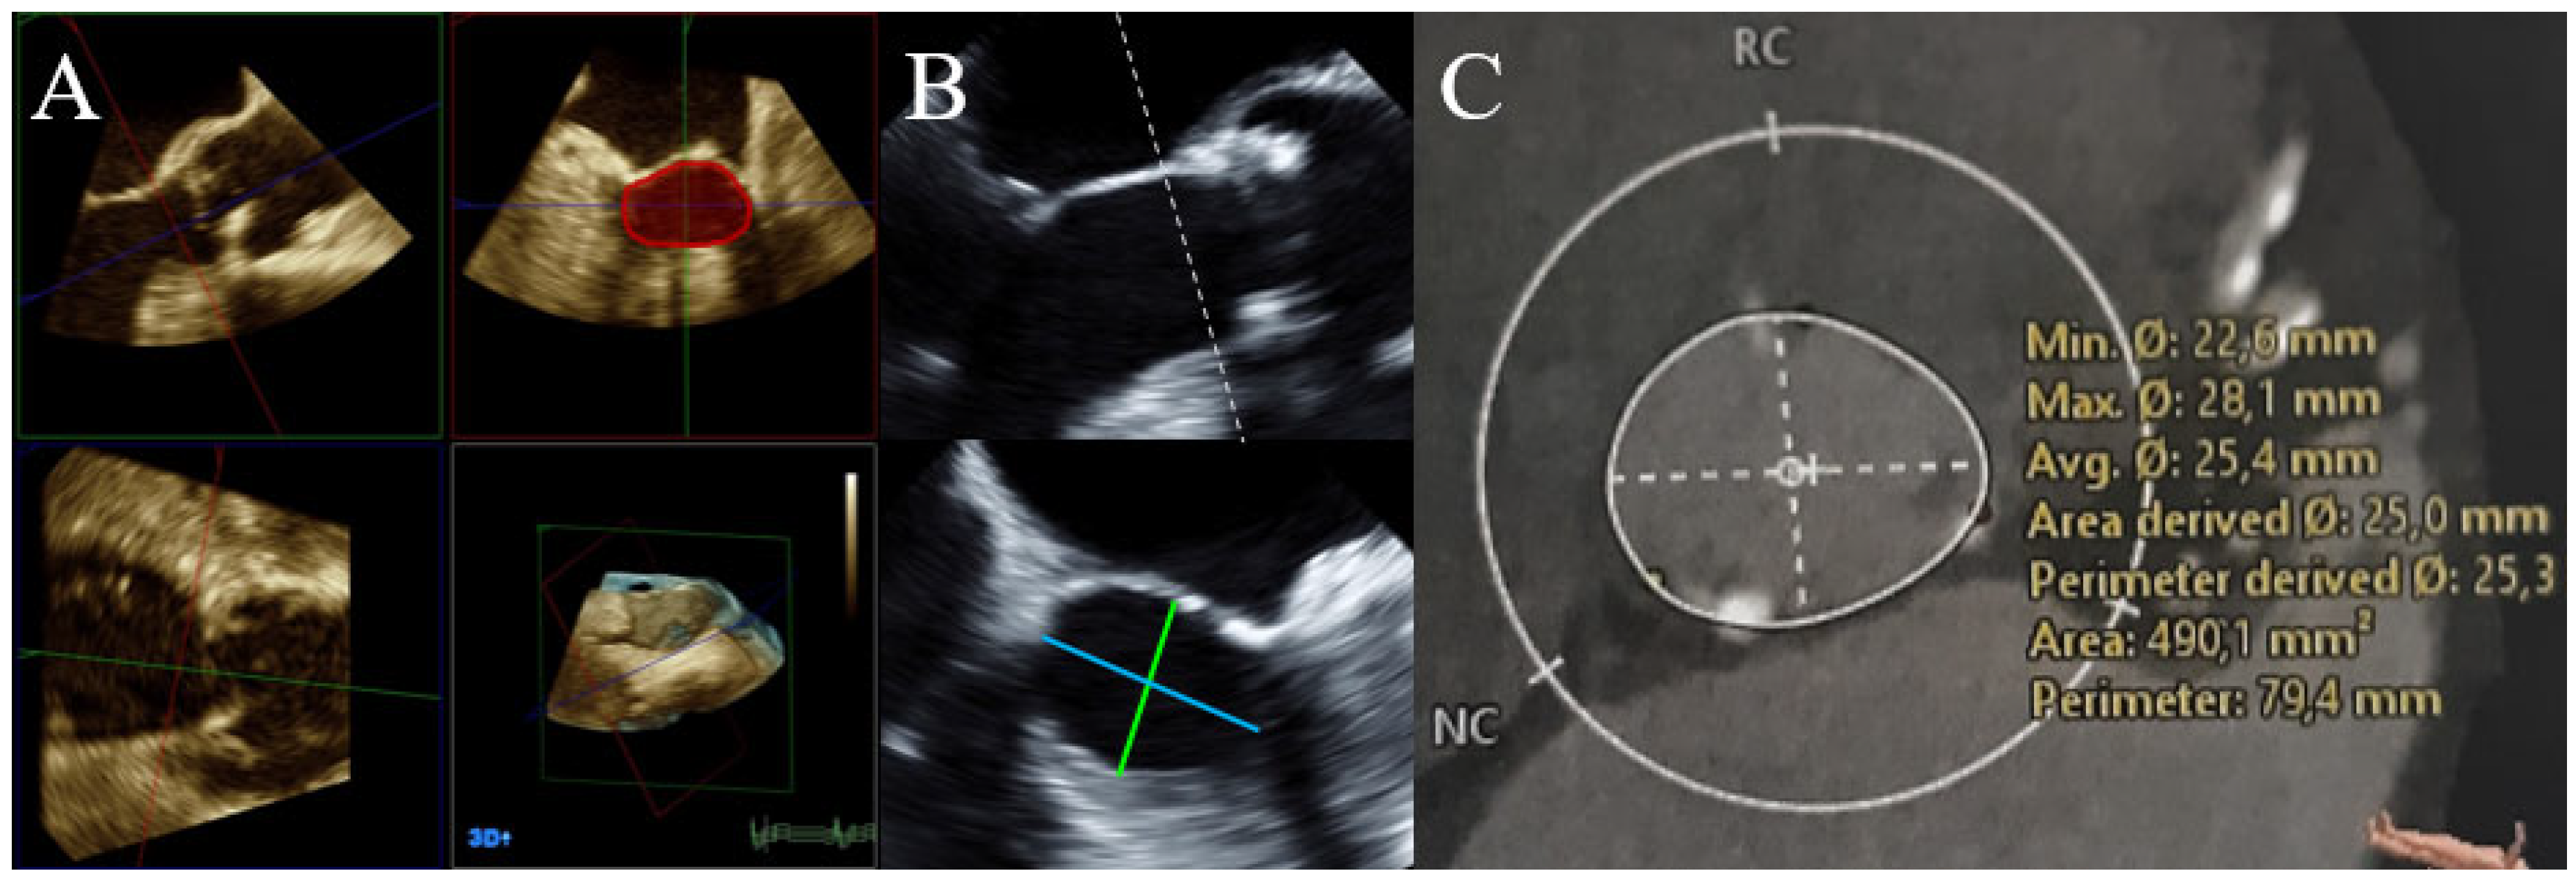

2.2. Echocardiography

2.3. CT